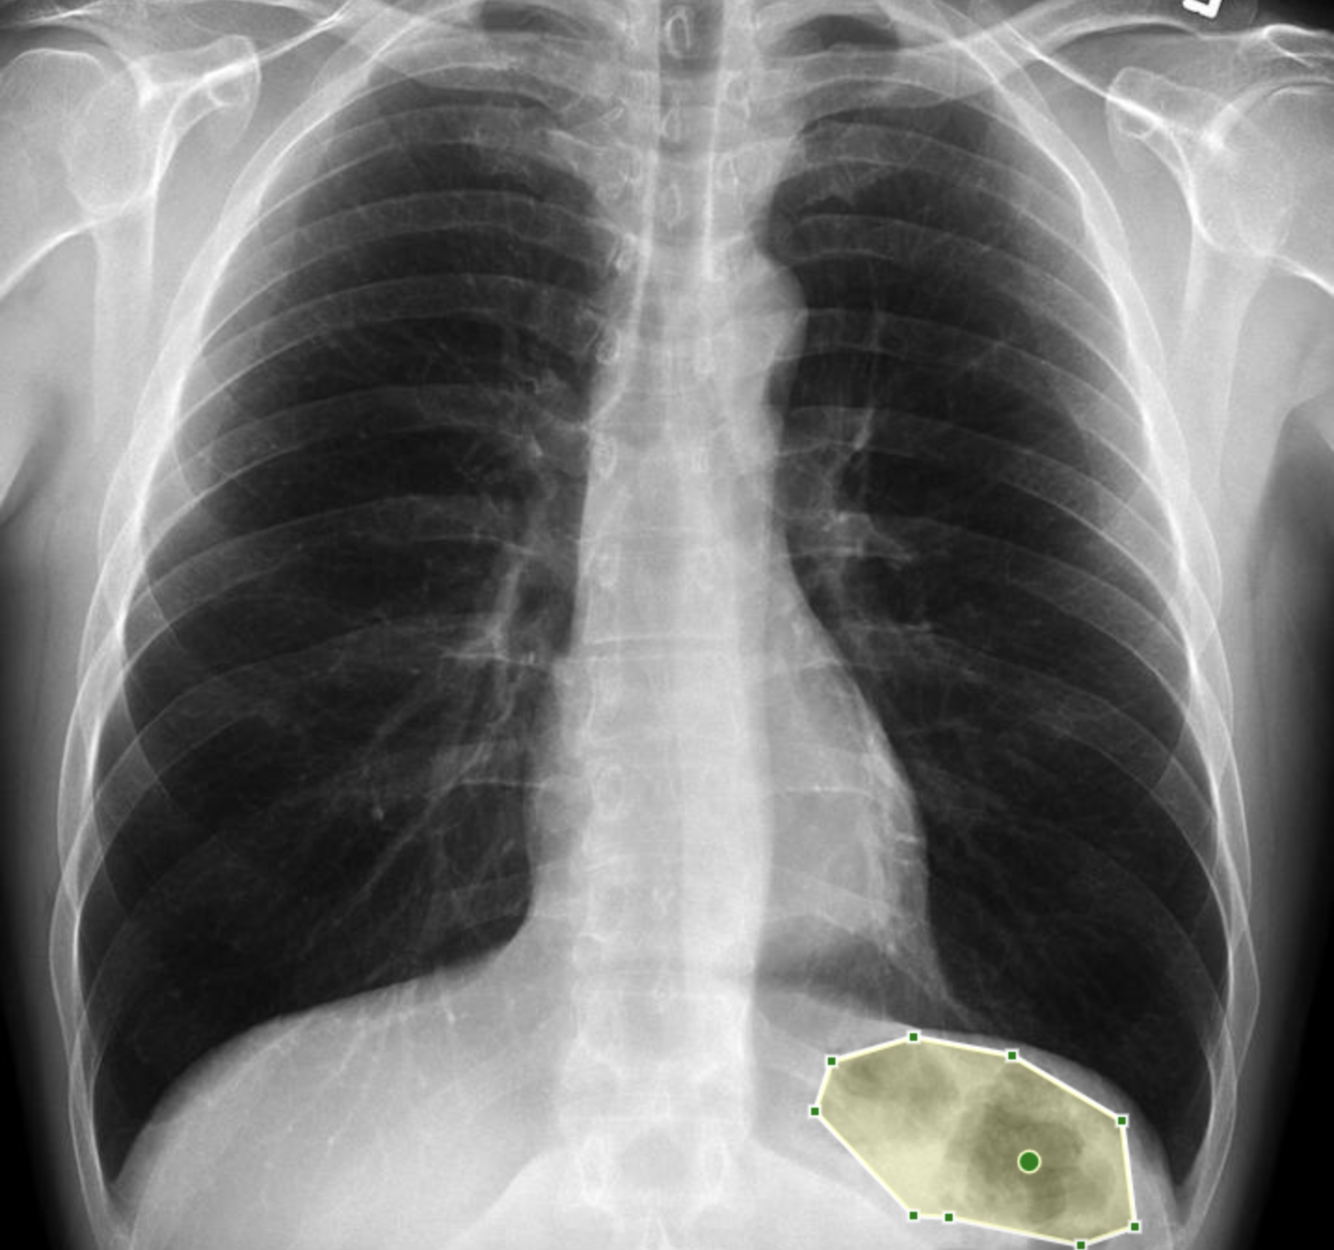

What pathology is shown in this chest x-ray?

Answer: Pulmonary oedema

What is being identified here?

Gastric bubble